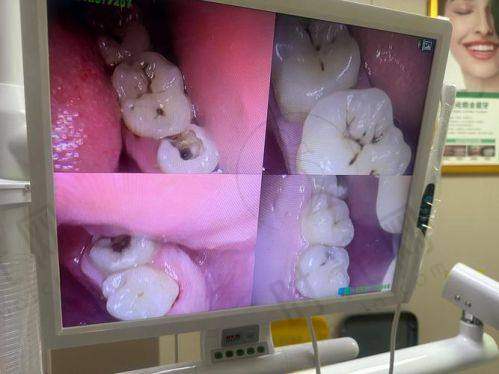

补牙拔牙及其他牙齿治疗相关费用也特别清晰。超声波洁牙180元起,能有效清洁牙齿;根管治疗580元/根起,解决牙齿疼痛问题;进口树脂补牙380 - 1080元/颗起,修复牙齿的外形和功能。

真相:种牙收费高并不一定就代表适合自己。不同的种植体品牌和医生技术对应不同的价格,患者应该根据自己的口腔情况和经济实力来选择。例如,对于单颗牙齿缺失的患者,如果口腔条件较好,选择价格相对较低的韩国登腾种植牙也能达到不错的成效,不一定非要选择价格高的瑞典诺贝尔种植牙。